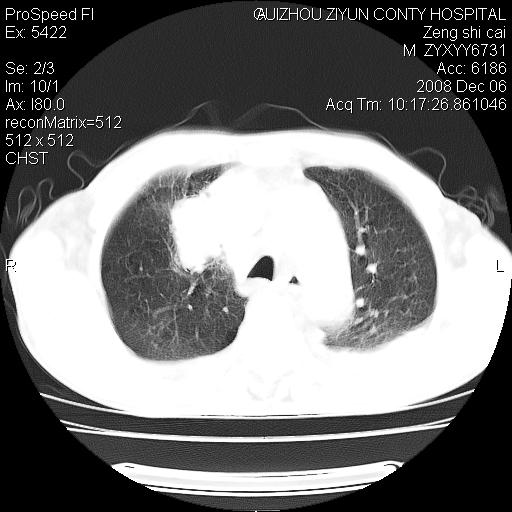

标题: CT16961:M、71岁,咳嗽半年,无血痰;胸片示右肺占位。 [打印本页]

标题: CT16961:M、71岁,咳嗽半年,无血痰;胸片示右肺占位。

右肺癌并纵隔淋巴结及胸膜转移可能性大

右肺癌并纵隔淋巴结及胸膜转移。建议气管镜

右肺纵隔型肺癌伴纵隔淋巴结及胸膜转移!

右肺纵隔型肺癌伴纵隔淋巴结转移!双侧胸水!

1)考虑右肺上叶纵隔型肺癌伴纵隔淋巴结转移。2)心包积液,双侧胸腔积液。

右肺癌并纵隔淋巴转移,腹膜后转移可能性大,两侧胸腔积液

右肺上叶纵隔型肺癌伴纵隔淋巴结转移。心包积液,双侧胸腔积液。

右上肺癌并纵隔淋巴结及胸膜转移。

建议强化!主要鉴别是淋巴瘤与肺癌淋巴结转移。

右肺纵隔型肺癌伴纵隔淋巴结及胸膜转移